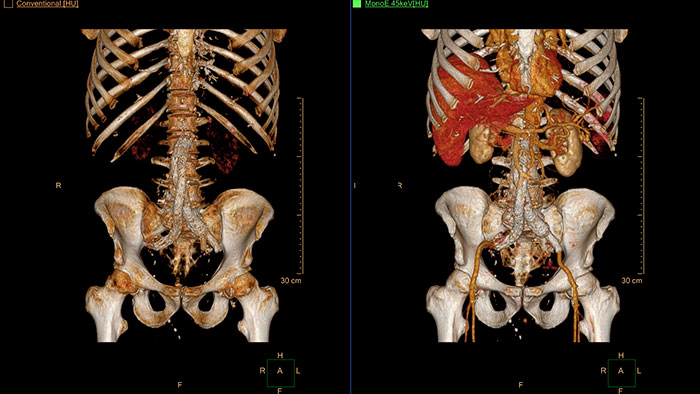

Visualize data from dual-energy acquisition

CT Dual Energy Viewer provides a set of tools for registration, quantification, and visualization of dual-energy image data acquired from the Philips iCT scanner’s sequential dual-energy acquisition.

Benefits

Allows retrospective use of spectral data that was saved as an SBI. Allows reviewing of spectral data and identification of most relevant result to be launched into the conventional CT application for routine work – even for applications that were not developed to support Spectral functionality.